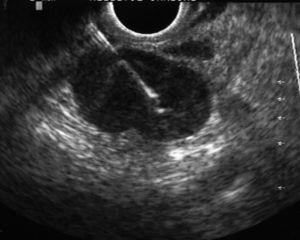

La USE-PAAF se realizó con un ecoendoscopio sectorial (GF UC30P, Olympus America Inc., Melville, NY, EE UU) y una aguja de Wilson Cook de 22 G y 8 cm de longitud (Wilson-Cook Medical Inc., Winston-Salem, NC, EE UU), según la técnica habitual: después de localizar la lesión a estudio con el ecoendoscopio sectorial, se introdujo la aguja a través del canal operativo del ecoendoscopio haciéndola avanzar hasta el interior de la lesión bajo control ultrasonográfico en tiempo real (fig. 3). El uso sistemático de Doppler color permitió descartar la existencia de vasos sanguíneos en el trayecto de la aguja. Tras retirar el estilete central de la aguja (que evita que la muestra obtenida en la punción se contamine con células de la pared del tubo digestivo), se aplicó una presión negativa entre 3 y 5 ml mediante una jeringa de 10 ml acoplada a la empuñadura de la aguja, mientras el ecoendoscopista realizaba movimientos repetidos de avance y retirada de la aguja dentro de la lesión.

Fig. 3. Punción aspirativa con aguja fina guiada por ultrasonografía endoscópica de una adenopatía mediastínica. Puede verse la aguja en el interior de la adenopatía.